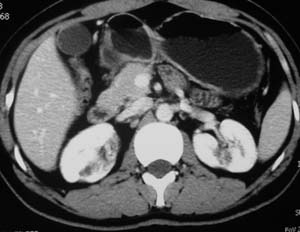

以下是引用子期在2010-3-19 20:47:00的发言:[br]血管畸形的ct增强应该有明显强化,本例并不相符合。本例双肾局部的略低密度影,累及肾盂,局部皮质明显变薄、内陷,增强扫描有轻度的强化,应考虑为炎性病变,患者为年轻男性,累及双肾的感染以结核较常见,可以没有明显的临床症状,尿中有时候也并不能查出什么;肾脓肿常有明显感染中毒症状,本例不符,另外一般的肾盂肾炎或肾小球肾炎通过小便就可确诊,其它还不能排除的是黄色肉芽肿性肾盂肾炎,然而单凭ct一般也很难鉴别。